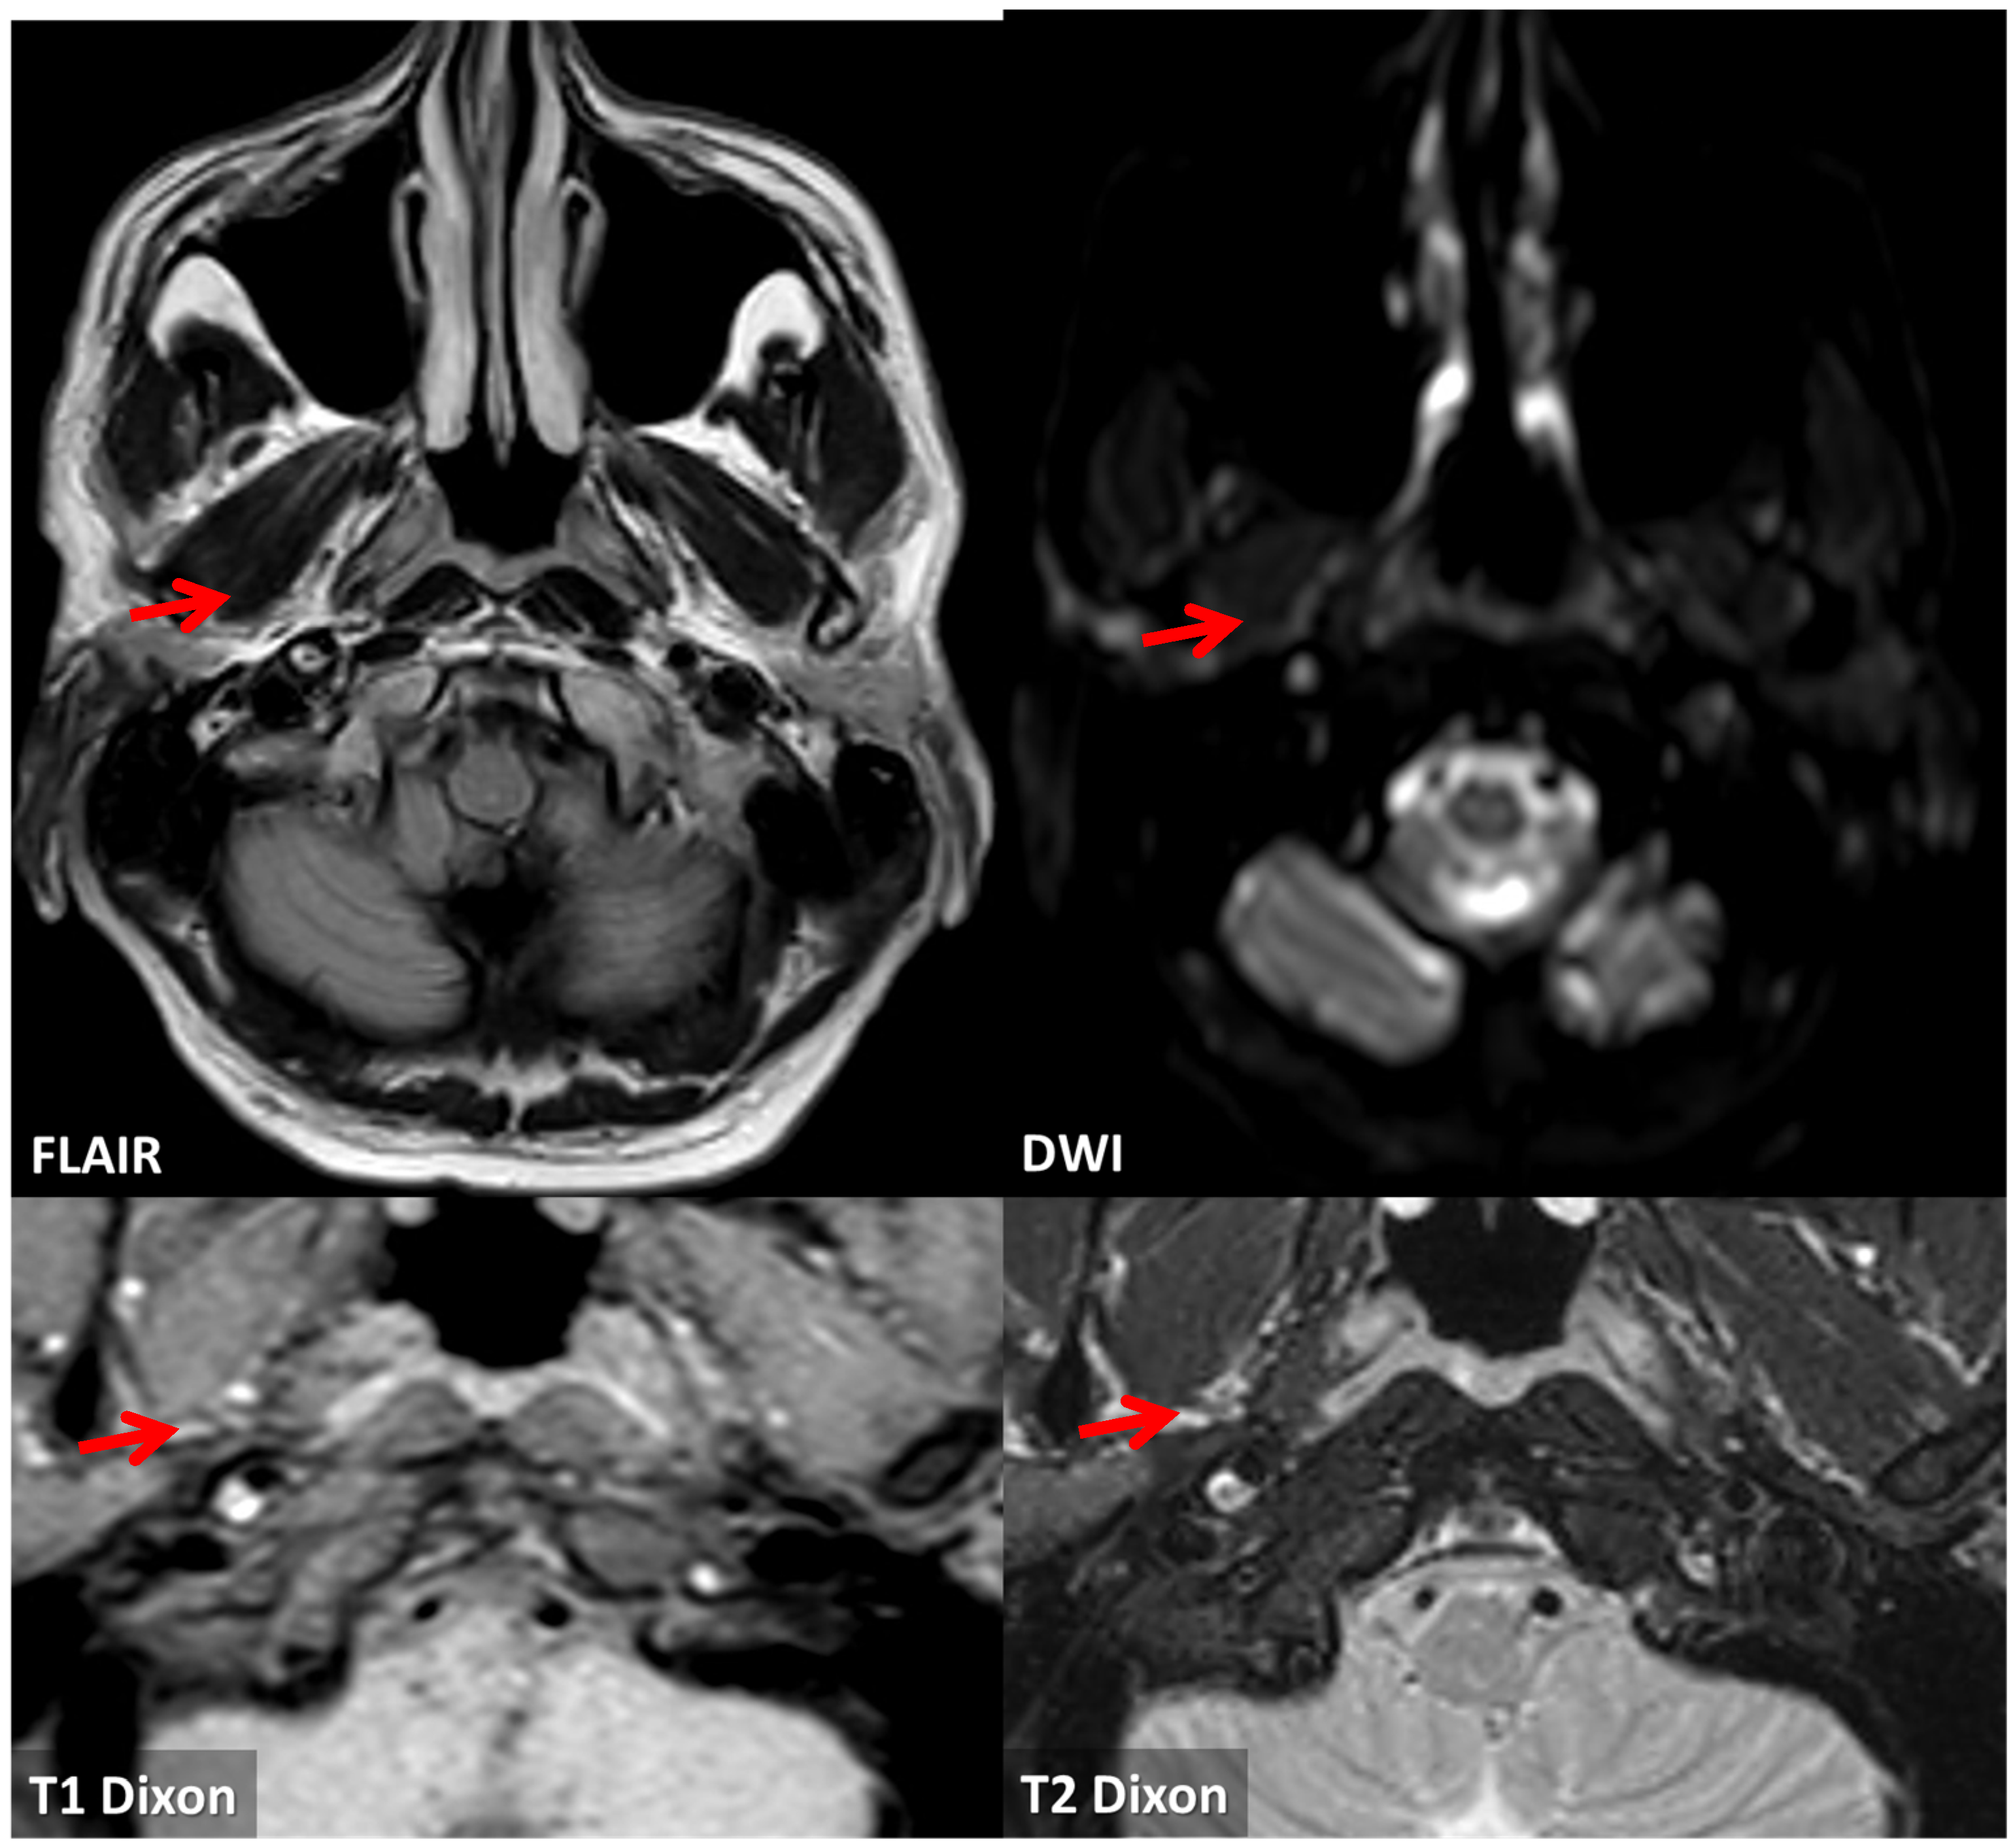

3.1. Case 1